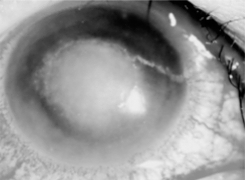

眼科専門用語で難しいですが、CL眼障害には点状表層角膜症、アレルギー性結膜炎、角膜潰瘍(写真1)・角膜浸潤、巨大乳頭結膜炎(写真2)などがあります。

角膜浸潤や角膜潰瘍は重症な場合は失明につながる場合があります。

写真1 角膜潰瘍